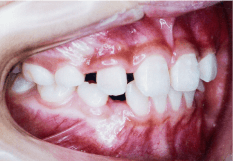

- 開咬(かいこう)

- 噛んでいても前歯がかみ合っていない状態のことで、発音が悪くなったり、前歯でものを噛み切ることが難しくなります。舌の癖や指をしゃぶる癖が原因で起こることがあります。

- 空隙歯列(くうげきしれつ)

- 歯と歯の間に隙間ができている状態で、顎の骨の大きさに対して歯が小さく生えてしまうことが原因です。

隙間があると食べ物が詰まりやすくなり、虫歯や歯周病の原因になります。また隙間から息漏れが生じるのでサ行・タ行・ラ行の発音が悪くなります。